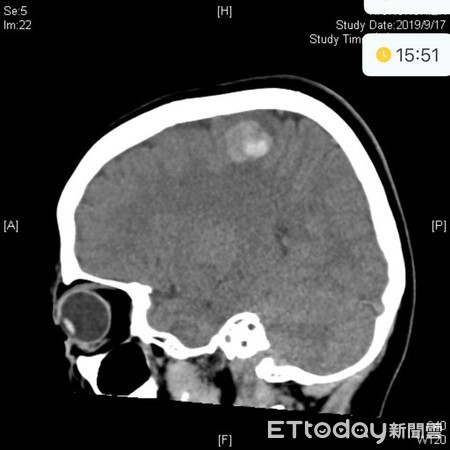

▲交完作業就倒地,少年送醫確診腦中風。(圖/吳昌騰醫師提供)

一名10多歲的少年,早上進教室教完作業給老師後,突然在老師面前倒地,且出現左側無力症狀,被校方緊急送醫,經電腦斷層檢查發現有顱內出血,確診腦中風。醫師提醒,許多人都以為中風是中老年人疾病,殊不知腦血管疾病也是兒童十大死因之一,家長若發現孩童有異常,千萬不能掉以輕心。

收治換的林口長庚兒童急診科主治醫師吳昌騰在「來講兒科急診的543」粉絲專頁上寫道,兒童腦中風通常是先天性血管異常,最常見的出血性兒童中風,主要是胎兒行形成時,腦部微血管發育異常,使得動脈血流不經過微血管而直接流入靜脈,形成蚯蚓般怒張的畸形血管,當靜脈承受不了那麼高的壓力時便會破裂。